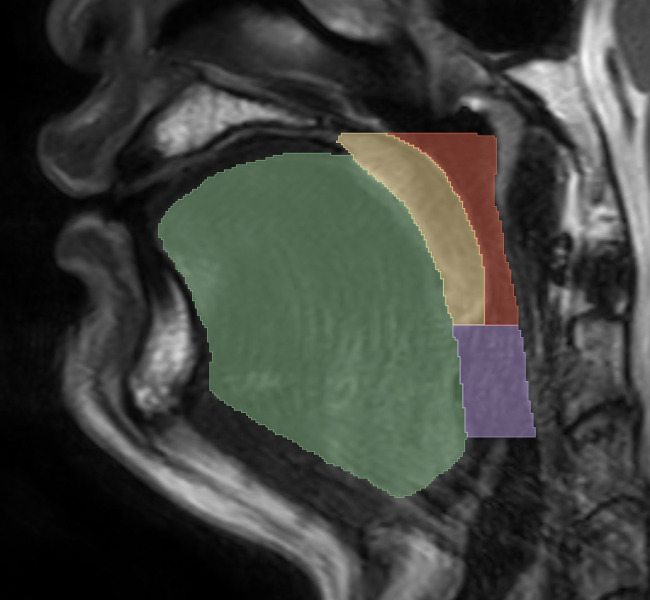

研究目的:本研究旨在评估结合咽部MRI放射组学和临床数据的模型在区分严重和非严重阻塞性睡眠呼吸暂停(OSA)方面的预测性能。方法:共纳入106例患者,其中48例患者AHI < 30 events/h, 58例患者AHI≥30 events/h。从MRI图像中提取放射组学特征。在应用最小冗余和最大关联以及Lasso与交叉验证进行降维之后,使用逻辑回归(LR)、支持向量机(SVM)、随机森林(RF)和梯度增强机(GBM)建立了放射组学模型。以年龄和BMI为临床特征,与放射组学特征构建联合模型。使用F1分数和接收者工作特征曲线(AUC)下的面积来评估模型的性能。结果:从MRI图像中提取了129个放射组学特征。通过降维和特征选择,确定了两个具有显著预测价值的放射组学特征。结合SVM (AUC=0.78, F1=0.75)、RF (AUC=0.78, F1=0.74)、GBM (AUC=0.79, F1=0.75)和LR (AUC=0.82, F1=0.80)的组合模型,与单纯基于放射组学特征的模型相比,表现出更优越的性能。仅放射组学模型包括SVM (AUC=0.76, F1=0.72)、RF (AUC=0.73, F1=0.67)、GBM (AUC=0.76, F1=0.73)和LR (AUC=0.78, F1=0.76)。在组合模型中,LR的预测精度和分类性能最高。结论:结合放射组学特征和临床特征的联合模型在区分重度和非重度OSA方面具有较好的能力。该方法为临床决策提供了一种无创、有效的新视角。

Methods: A total of 106 patients were included in the study, with 48 patients having an apnea-hypopnea index < 30 events/h and 58 patients having an apnea-hypopnea index ≥ 30 events/h. Radiomics features were extracted from magnetic resonance imaging images. After applying minimum redundancy and maximum relevance and least absolute shrinkage and selection operator with cross-validation for dimensionality reduction, radiomics models were developed using logistic regression, support vector machine, random forest, and gradient boosting machine. Age and body mass index were used as clinical features to construct a combined model with radiomics features. The performance of the models was evaluated using F1 scores and the area under the receiver operating characteristic curve (AUC).